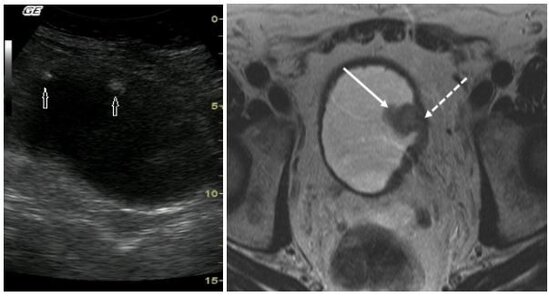

Uroloqlar onun sidik kisəsində böyük yad cisim aşkarlayırlar. Əməliyyat zamanı çıxarılan yad cisimin tamamilə kristallaşmış stəkan olduğu görülüb.

Bu müddətdə stəkanın ətrafında 8 sm diametrində minerallaşmış daş yaranıb.